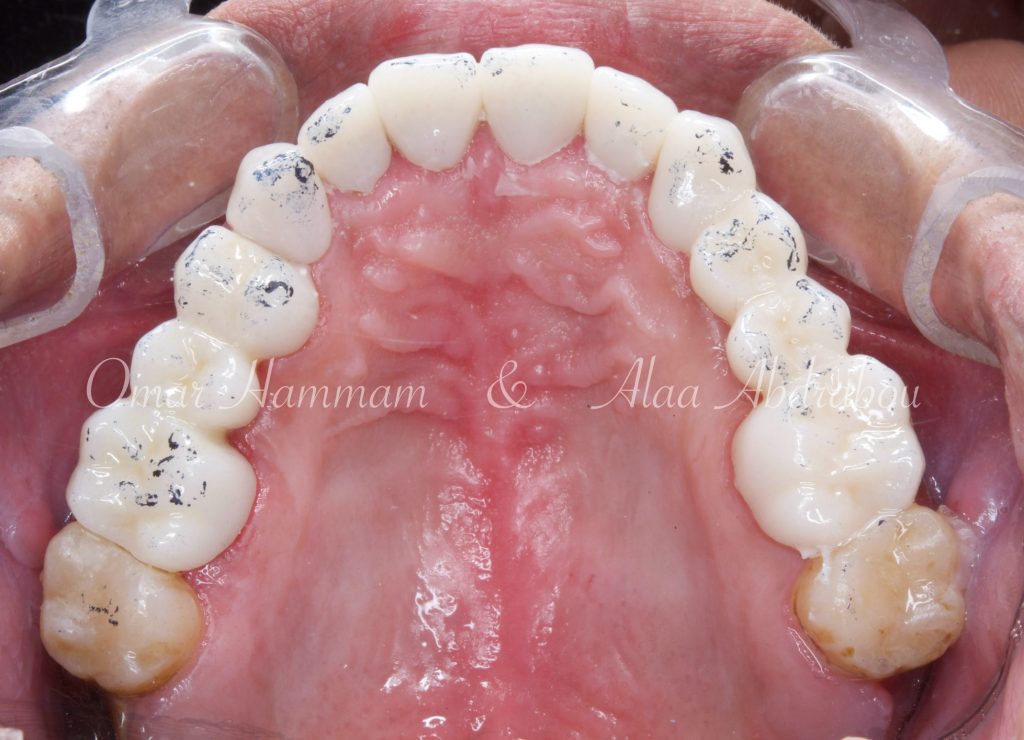

Immediate occlusal scheme after cementation (before any adjustments):

Showing “Occlusal equilibration”, where Stable occlusion is achieved , in which there are Stable contacts of equal intensities on all teeth in centric occlusion showing Group Function occlusion.

Occlusal forces are distributed on more occlusal contacts, Acting as a group to distribute occlusal forces, thereby increasing efficiency of mastication and performing lateral movements atraumatically.